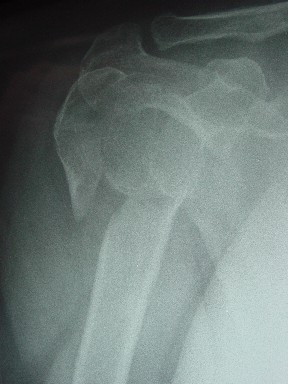

Здесь случай перелома-вывиха плеча, больному 56 лет, после "дважды" закрытой неудачной репозиции, опять же ургентно взяли в операционную, после полного общего обезболивания попытались сделать репозицию, и фиксацию провели спицами.

Больной находился в повязке, примерно напоминяющей косыночную, рекомендованы движения в локтевом суставе и маятниковые движения в плече, спицы удалены в три недели (были случаи миграции)

Больной амбулаторный, предупрежден на случай осложнения АВН головки.

Клинические снимки - 3 недели после операции

с уважением М. Беренштейн